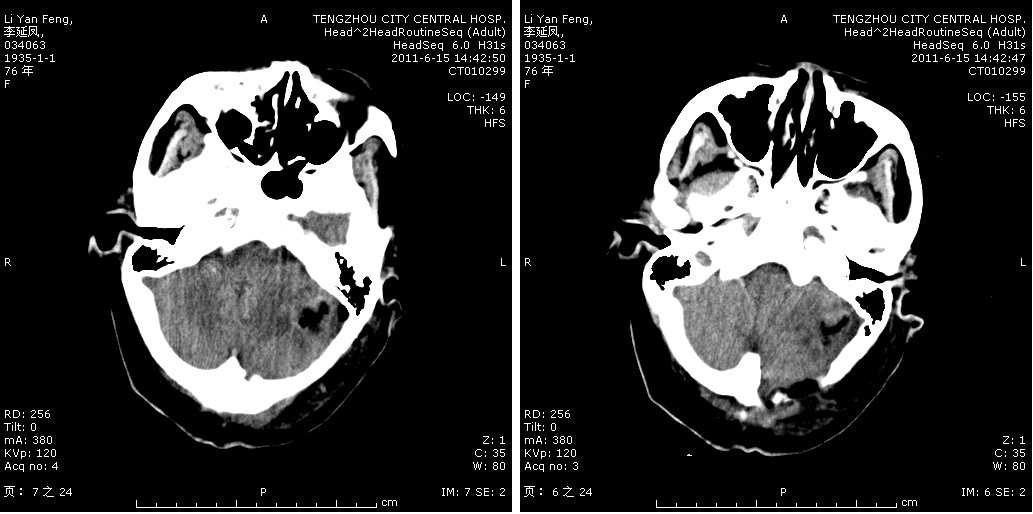

轉移瘤切除術前

轉移瘤切除術后